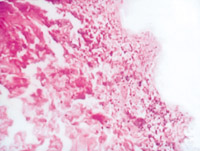

5-2-1 伤后第1天,,,,表皮凝固性坏死,,,,真皮浅层胶原纤维变性  HE×100